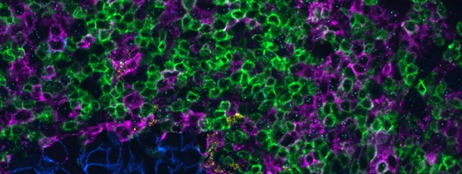

대장암에서 공동 검출로 CD4+ / FOXP3+ regulatory T 세포와 CD8+ / IFNG+ 세포독성 T 림프구를 시각화하였습니다.